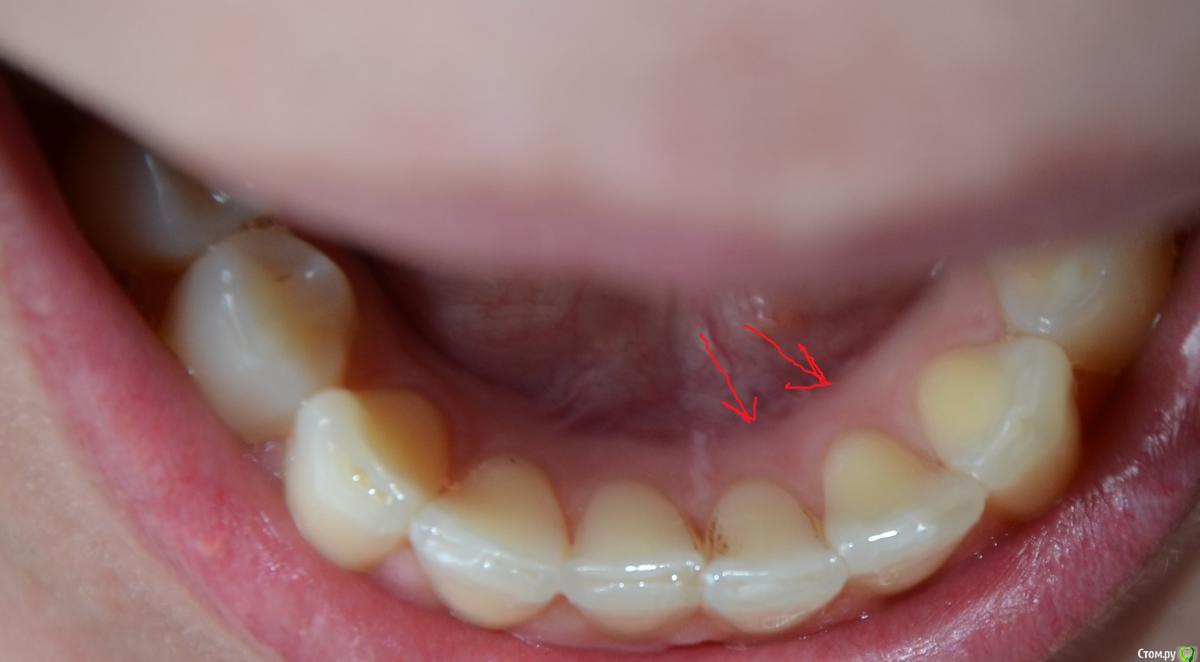

Olga82 Опубликовано 24 апреля, 2015 Поделиться Опубликовано 24 апреля, 2015 Прошу совета в нижеследующих проблемах:Зубы начала лечить с января 2105 года(Рентген-снимок именно до лечения прилагается), вылечила уже все зубы кроме одного(26-й или 16-й, не знаю, с какой стороны правильно вести отсчет).Проблема №1:Сделали верхние передние(замена пломбы+выравнивание режующей поверхности посредством пломб на обоих зубах+полировка(шлифовка).После шлифовки появились сначала белый точки, потом на зубе 1(фото прилагается) при чистке зубов прямо отошел тонкий кусочек как пленка полупрозначная зуба(зуб вообще был здоровый, только неровный рез), теперь там выемка как бы вглубь), на зубе 2 сейчас неровная как неотшлифованная поверхность (на фото, к сожалению, плохо видно, невозможно снять), на зубе 3 идет полоса на эмали-опять-таки как дефект шлифовки.Как это понимать? Топорная шлифовка или мои проблемы с зубами? дело в том, что я кормлю грудью уже 2 года, мой стоматолог сказал, что в зубах судя по всему мало кальция, поскольку после несильной заморозки один из них быстро побелел.Что мне предпринять? Дошлифовать недошлифованное?Или не трогать, а провести реминерализацию/глубокое фторирование/пропить курс витаминов и только потом их трогать? Какова судьба моих любимых передних зубов-печальная или смотреть оптимистично? Проблема №2:Дней пять как стали ныть нижние зубы(по фото обвела), их не лечили, они вроде как здоровые, небольшой коричневый налет присутствует с внутреннего края на одном, стоматолог его немного поскреб ....и смолчал...ничего не сказал...это камень, я правильно понимаю?Боль постоянная, тупообразная.Я полна мыслей об отстутствии кальция в моих зубах и слабости эмали купила пасту Лакалют сенситив, чищу ей второй день-пока нет результата, как болело, так и болит, полощу ротовую полость содой.Что это может быть?К стоматологу записана на 3 мая, не знаю, доживу ли до этого срока.Надо срочно бежать ?Спасибо всем за уделенное время моим проблемам. Ссылка на комментарий

Olga82 Опубликовано 25 апреля, 2015 Автор Поделиться Опубликовано 25 апреля, 2015 Вас сюда на задание Шон Коннер отправил? Да все что не дополировано, дополировать А у меня зубы не начнут сыпаться-откалываться? Меня пугает, что на каждом полированном белые точки появились(возможно это воздух?), и что произошел скол эмали с №1.До полировок с зубами подобного не происходило.так можно дополироваться до постановки виниров(Нет? В чем может быть причина ноющей боли в нижних передних? Как мне можно её снять до визита к врачу?(несколько дней).Это болезнь десен или чувствительность зубов по большей вероятности? Ссылка на комментарий

faity Опубликовано 25 апреля, 2015 Поделиться Опубликовано 25 апреля, 2015 я написал офигительно длинный пост и случайно все удалил(((поэтому вкратце: отчего могут быть сколы эмали на зубах после полировки и белые точки? сколы из-за неправильного распределения нагрузки во время жевания, неправильное распределения нагрузки- из-за неправильного прикуса, пятна либо недополировали, либо после полировки покрыли адгезивом, чтобы "блястело сразу в кресле" Это чёй-то? У меня показания к удалению только одного зуба(я с номерами уже запуталась, он наверху). показания ортодонтические .Мой врач сказал, что прикус нормальный, без претензий на идеальность, но жить можно без ущерба здоровью зубов.Вы считаете, что в этом есть обязательная необходимость? Прикус патологический и если эстетика вас не напрягает, то артрит височно-нижнечелюстного сустава начнет рано или поздно давать о себе знать. Плюс читайте выше про ударные нагрузки и к чему это приводит. Ссылка на комментарий